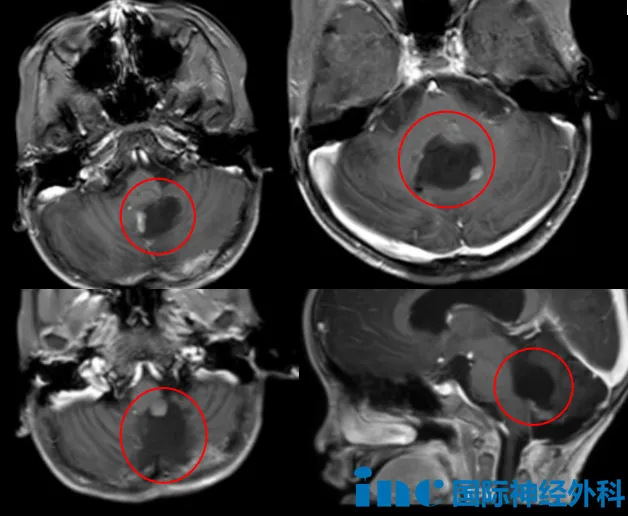

5岁男性患儿布布确诊为后颅窝室管膜瘤,此前经历两次开颅手术和一次质子治疗,但肿瘤再次复发。患儿年龄小、体重轻、血容量低,肿瘤深度嵌入脑干背侧且呈多发性生长。2023年因走路不稳发现颅内肿瘤,同年9月接受首次后颅窝肿瘤切除,术后病理诊断为室管膜瘤。2024年5月肿瘤复发,二次手术后病理升级为间变性室管膜瘤(WHO 3级),术后出现斜视、四肢无力、吞咽困难、言语迟缓等神经功能损伤。完成质子放疗后近期复查显示术区边缘出现可疑结节,与延髓紧密粘连。

术中发现实际情况较影像显示更为复杂:MRI增强扫描仅显示3处强化灶,但开颅后发现有更多未显影的肿瘤病灶。手术过程中患儿心率和血压出现波动,巴特朗菲教授保持沉稳操作,精准推进每个手术步骤。